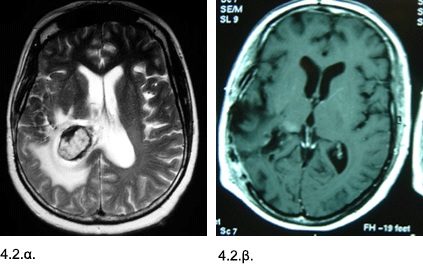

Εικόνες 4.2.α. & 4.2.β. Η προεγχειρητική μαγνητική τομογραφία (αριστερά) δείχνει με ευκρίνεια την μάζα του σηραγγώδους αιμαγγειώματος να ξεχωρίζει μέσα στην λευκάζουσα περιοχή οιδήματος και αιμορραγίας. Η μετεγχειρητική μαγνητική τομογραφία (δεξιά) δείχνει ότι το σηραγγώδες και το αιμάτωμα έχουν αφαιρεθεί μέσα από ένα περιορισμένο “διάδρομο προσπέλασης” χωρίς βλάβη στους παρακείμενους ιστούς.

Ιστορικό: Aσθενής 52 ετών με κεφαλαλγία, μείωση οράσεως και οίδημα οπτικών θηλών. Διαπιστώθηκε αιμορραγία που είχε προκληθεί από ρήξη σηραγγώδους αιμαγγειώματος. Έγινε κρανιοτομία και αφαίρεση του σηραγγώδους αιμαγγειώματος και αιματώματος. Η μετεγχειρητική πορεία ήταν ομαλή. Ο ασθενής δεν ανέπτυξε άλλα νευρολογικά προβλήματα, πέραν της μείωσης της όρασης, η οποία σταδιακά βελτιώθηκε.